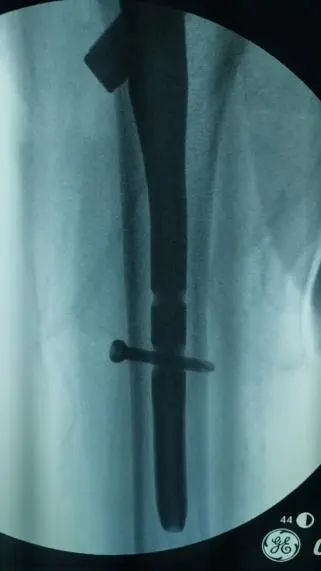

骨科团队迅速评估病情,认为手术治疗是让老人重新站起来的唯一希望,也是降低长期卧床并发症风险的最佳选择。在科主任李忠教授带领下,唐炼副主任医师团队反复研究影像资料,精心设计创伤小、固定可靠的手术方案——微创闭合复位股骨近端防旋髓内钉(PFNA)内固定术。手术仅用时30分钟顺利完成。